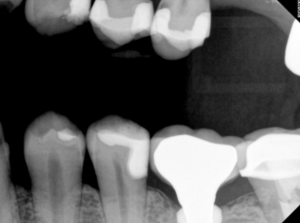

#7 MIFL, #8 MIFL, #9 MIDFL, #10 DL

#6 MF, #7 MDF, #8 DF, #9 DF, #10 MDF, and #11 MF